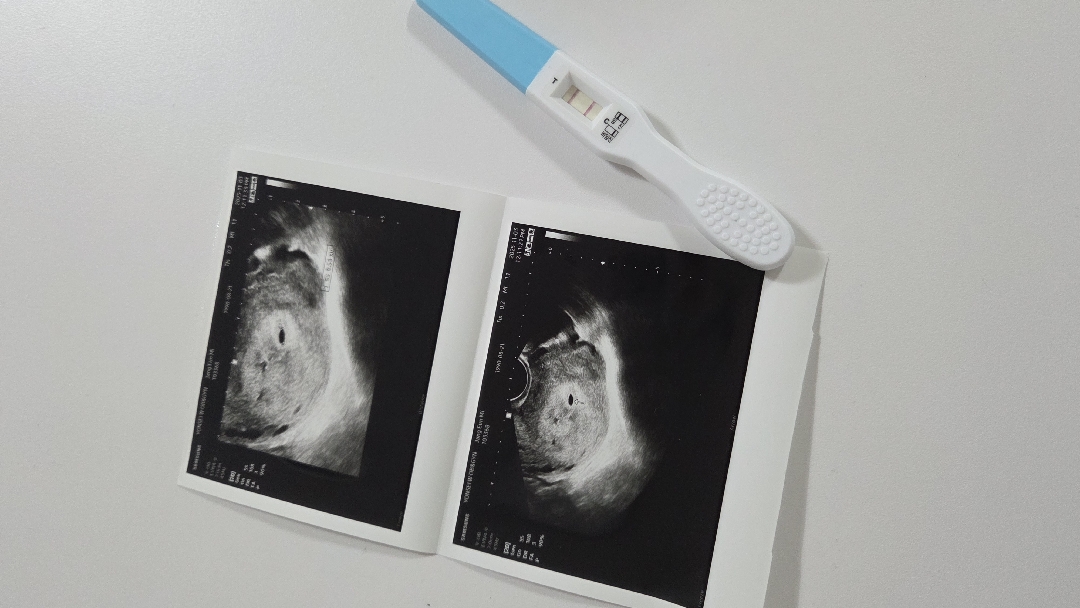

주차계산대비 아기집이 작아용

주차로는 6주2일이거든요 초음파 촬영당시에는 5주5일차였는데 좌측에는 피고임현상이구... 지금 증상으로는 출혈은 하나도 없으나 느글거림과 졸림과의 싸움중이에요ㅠㅠ